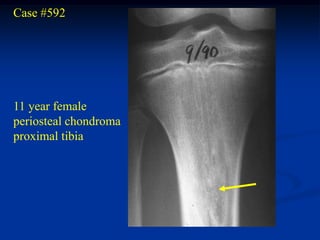

Case #592

11 year female

periosteal chondroma

proximal tibia

Another view

CTscan

Axial proton density MRI

Photomic